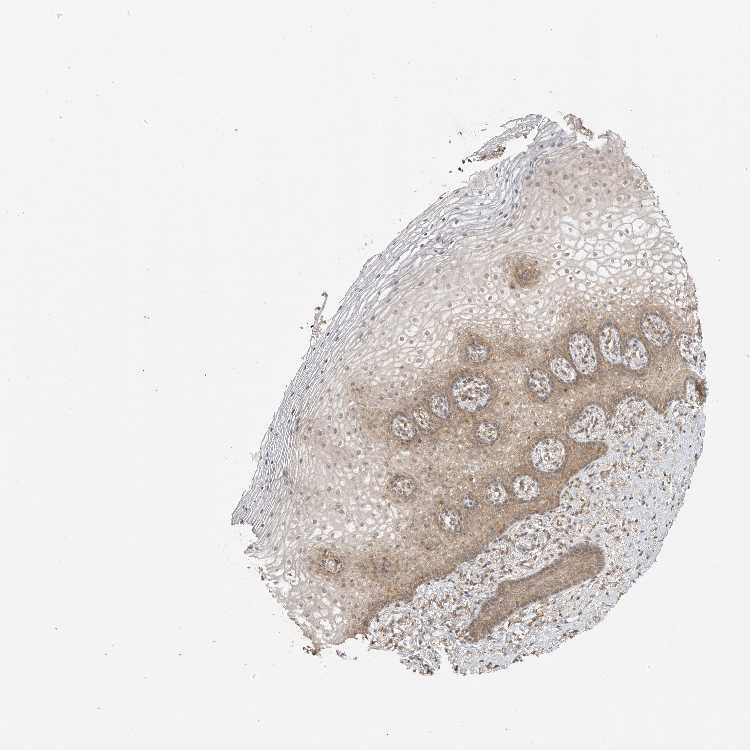

VAGINA - Antibody stainingi

Antibody staining in the annotated cell types in the current human tissue is reported as not detected, low, medium, or high, based on conventional immunohistochemistry profiling in selected tissues. This score is based on the combination of the staining intensity and fraction of stained cells.

Each image is clickable and will lead to virtual microscopy that enables deeper exploration of all samples and also displays staining intensity scores, fraction scores and subcellular localization as well as patient and tissue information for each sample.

Antibody CAB025423

Squamous epithelial cells Medium